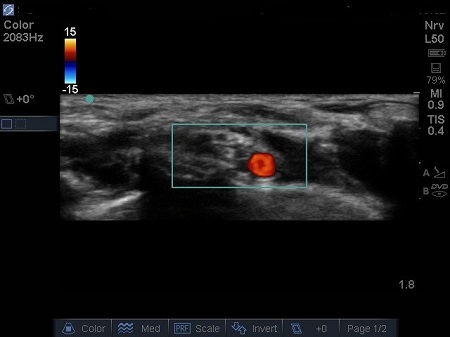

- The first structure to locate is the round pulsating hypoechoic subclavian artery (A), lying on top of the hyperechoic first rib (R). Use Doppler to assess for vessels. See Fig. 2.

Fig. 2. Bidirectional Doppler used here to highlight the subclavian artery.

Hypoechoic vessels may be seen among the brachial plexus nerves (also round hypoechoic structures). Because they have similar appearance, it is important to differentiate them (colour Doppler MUST be used) (16). See Fig. 9.

Fig. 9. Doppler highlighting subclavian artery with dorsal scapular artery passing posteriorly through brachial plexus.